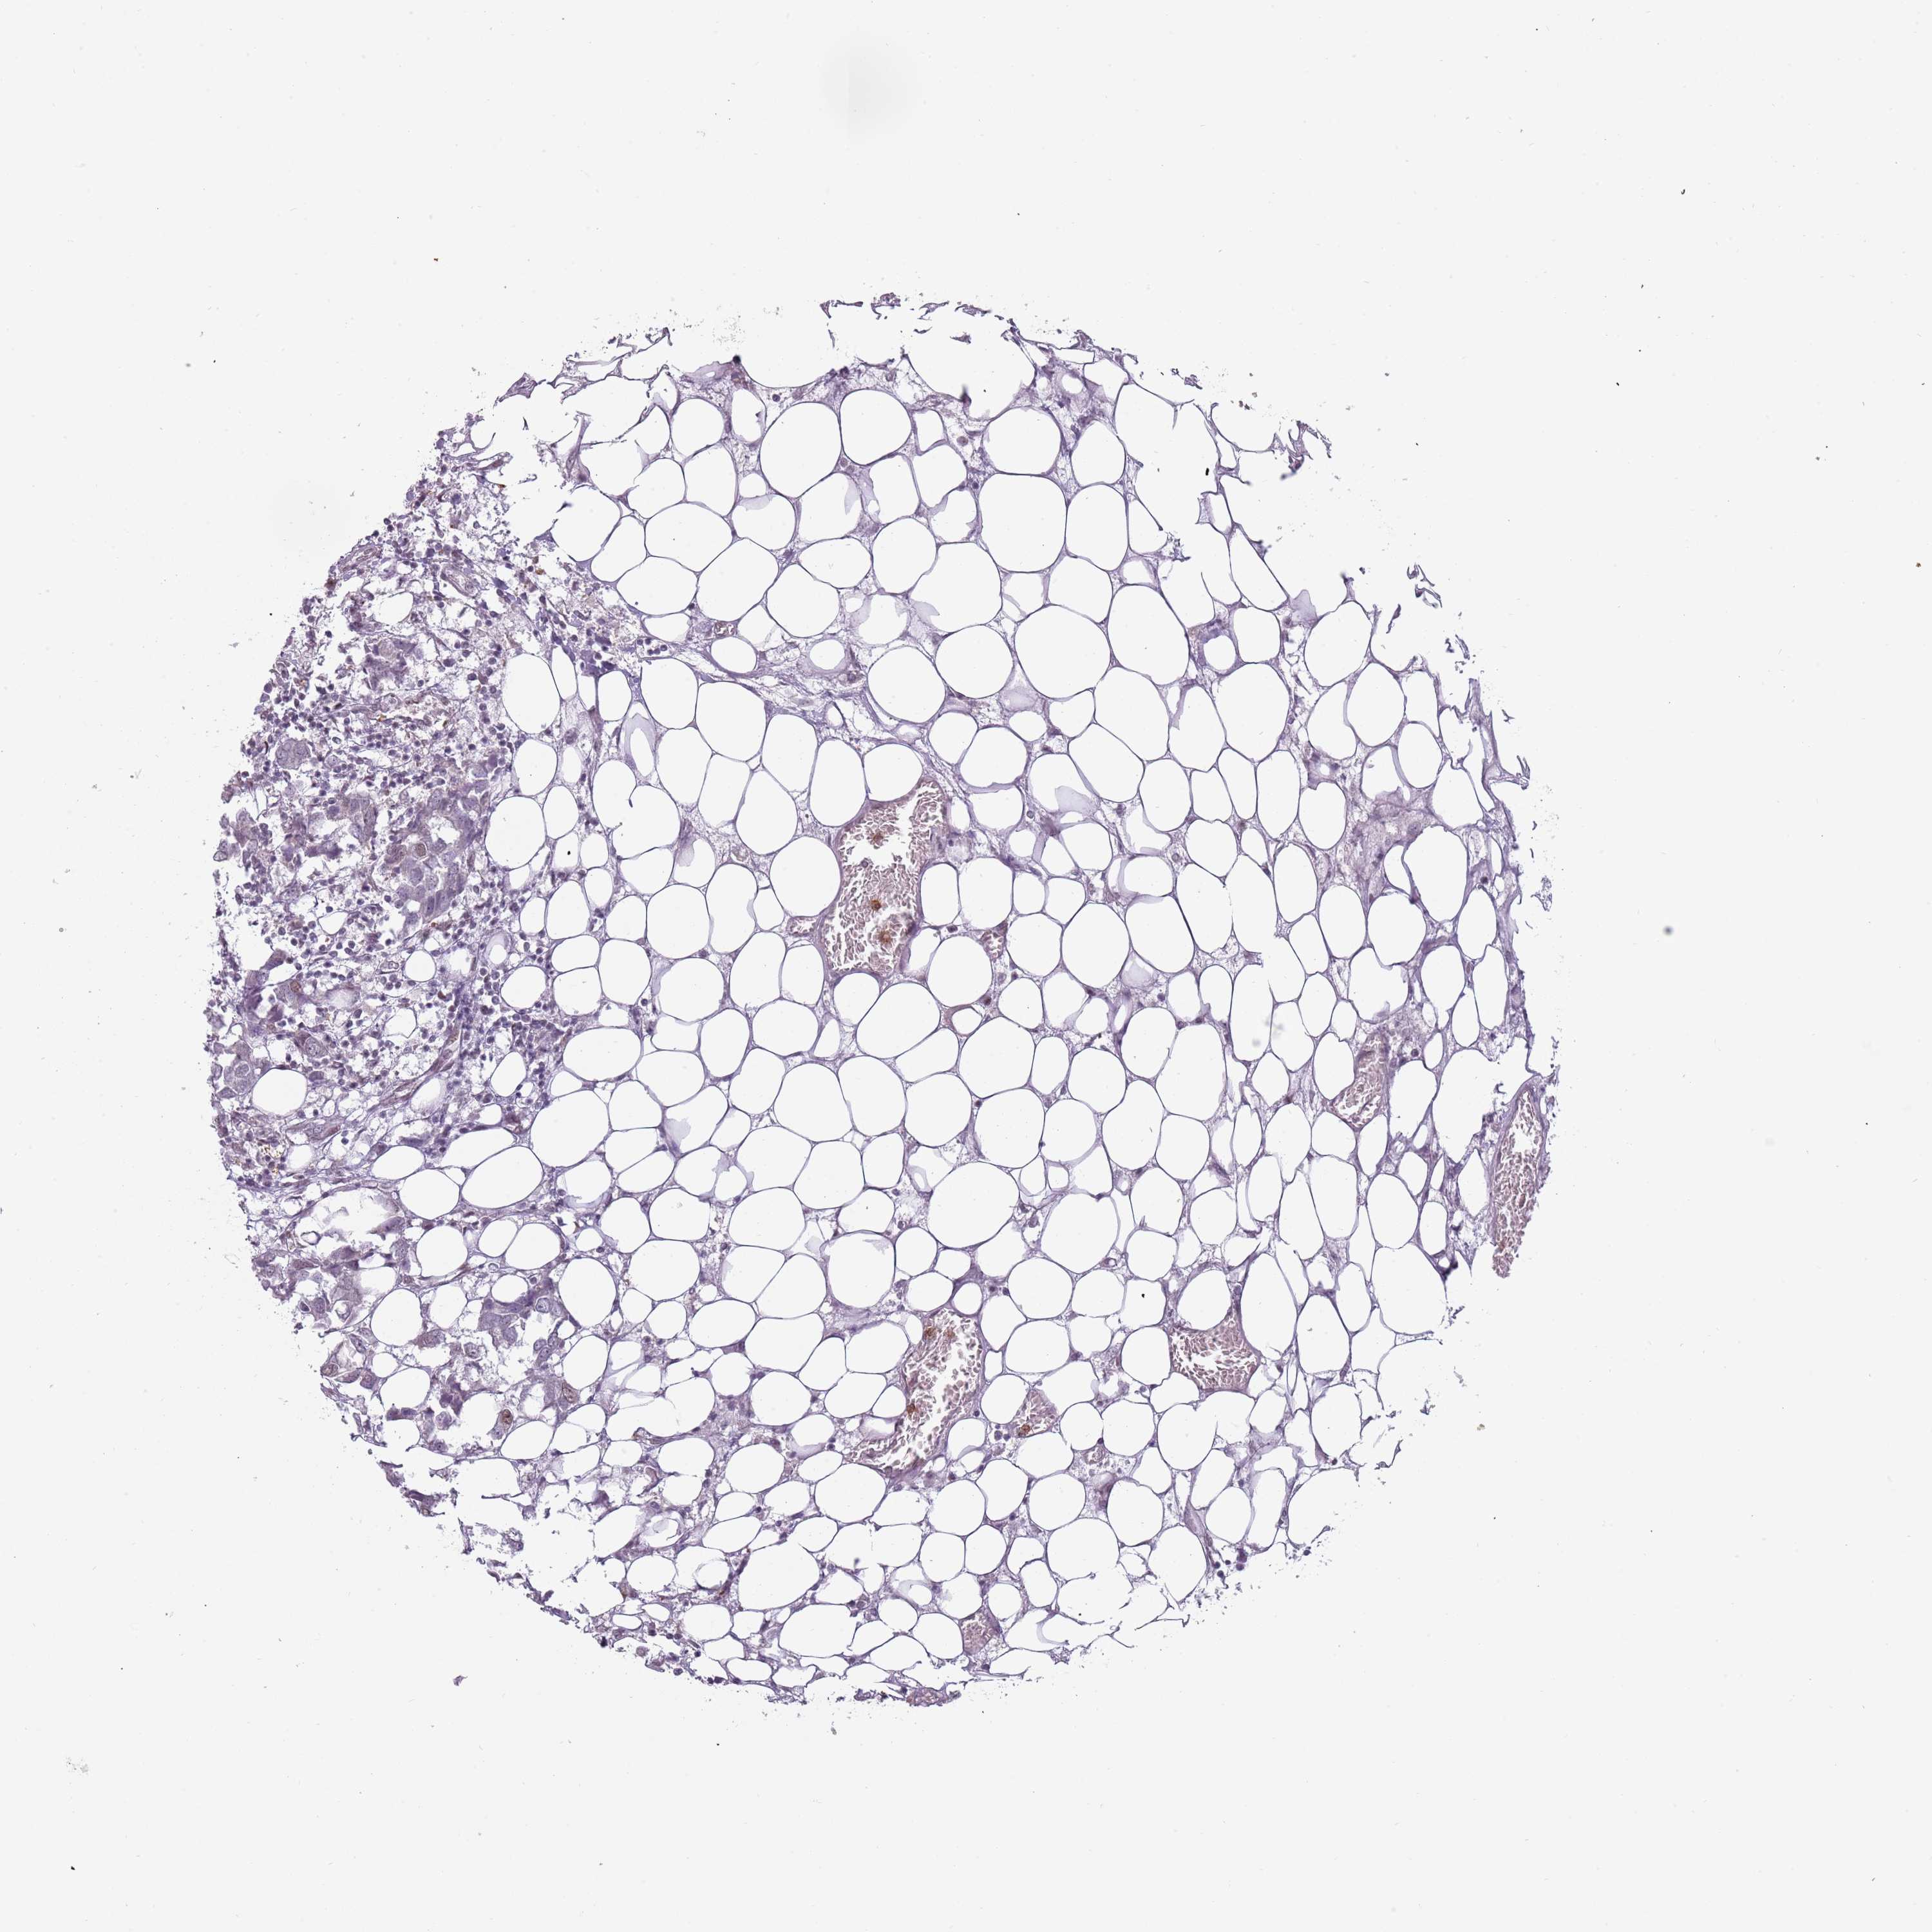

CANCER BREAST CANCER Show tissue menu

BRCA TCGA BRCA VALIDATION PROTEIN EXPRESSION